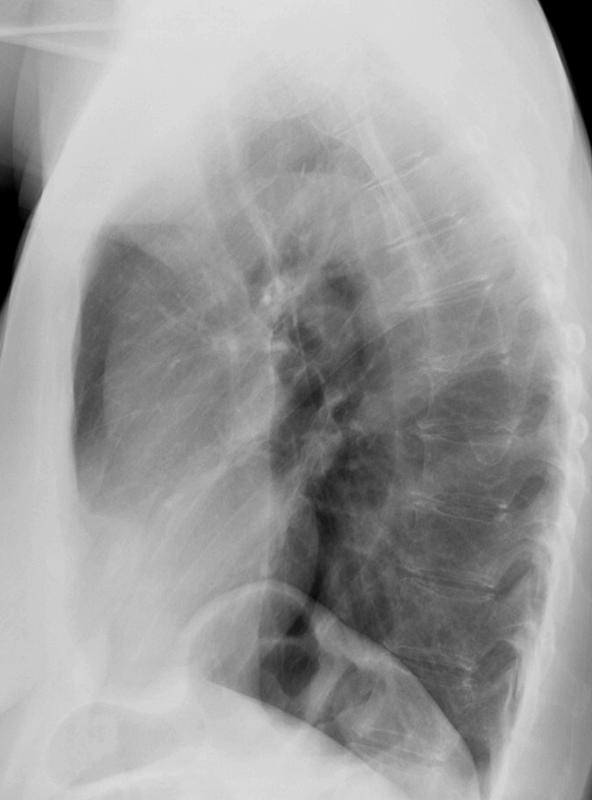

Scleroderma esophagus